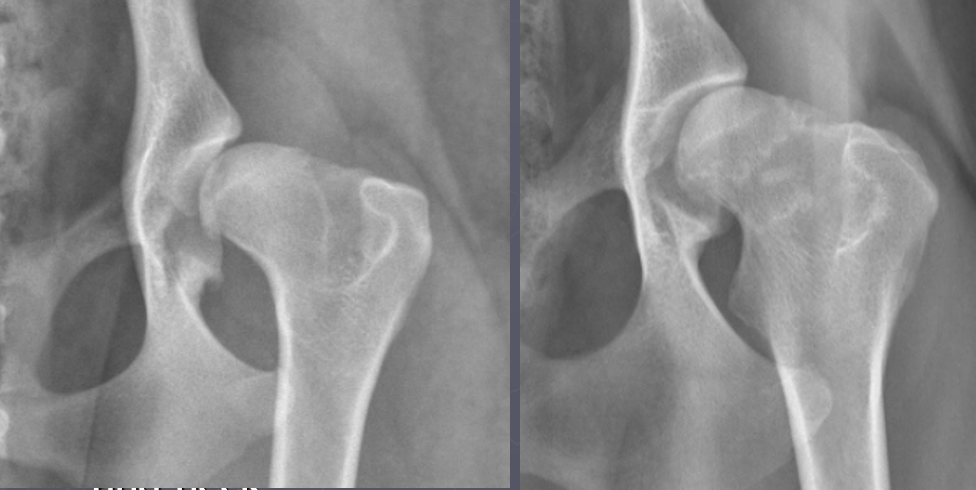

What is outlined in these radiographs?

A

Morgan’s line